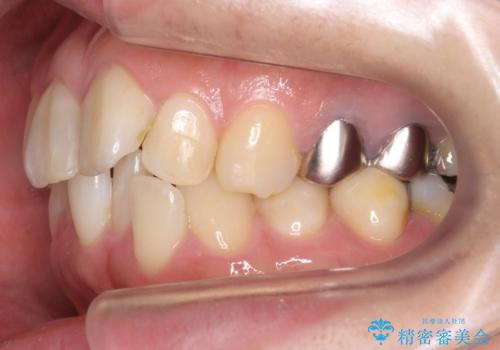

- 前歯の歯並びが気になることを主訴に来院された患者様です。

接客業のためインビザライン(マウスピース矯正)をご希望されました。

顎が小さく歯を並べるためのスペースが足りないため、

上下の前歯の歯と歯の間をすく処置(ディスキング)を行いました。

矯正装置:インビザラインフル (初回13stage+リファインメント11stage:計1年)

矯正後、右上5左上45セラミッククラウン・右下65左下5セラミックインレーによる補綴治療を行いました。

なお、左下の奥歯(左下7)は状態が悪く保存不可能と判断し矯正前に抜歯しております。